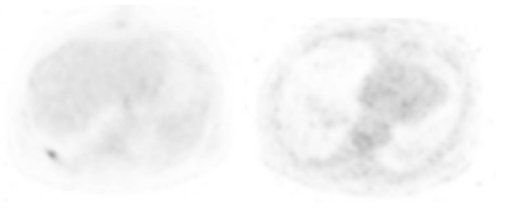

Patient was discharged from the hospital at day 22. Control PET/CT was negative and no longer showed the hepatic lesion on segment VII (Figure 4). Colonoscopy was performed 6 months after the first surgery without significant findings, and he underwent re-connection of the colon transit through a laparoscopic approach. The metastatic nodule over the liver was searched for even with the laparoscopic ultrasound and indocianyne green, but it was no longer found. The patient had an uneventful recovery from the surgery, tolerated oral diet on day three, and was discharged from hospital on day five. Patient is still in close follow-up receiving adjuvant chemotherapy to this day without any evidence of recurrence, and doing his daily routines uneventfully.

Figure 4 PET scan of the liver seven days after initial surgery (A) and six months after (B). Taken with permission of the patient, in the archives of Alejandro Weber M.D. chief surgeon.